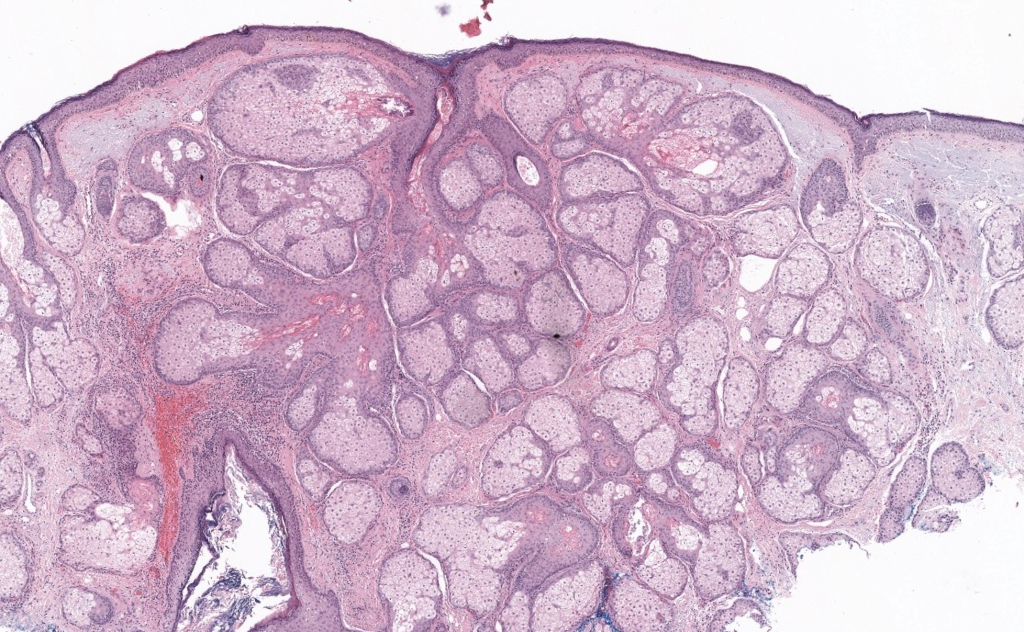

- Histología: lóbulos sebáceos aumentados con sebocitos maduros alrededor de ducto infundibular dilatado, sin atipia.